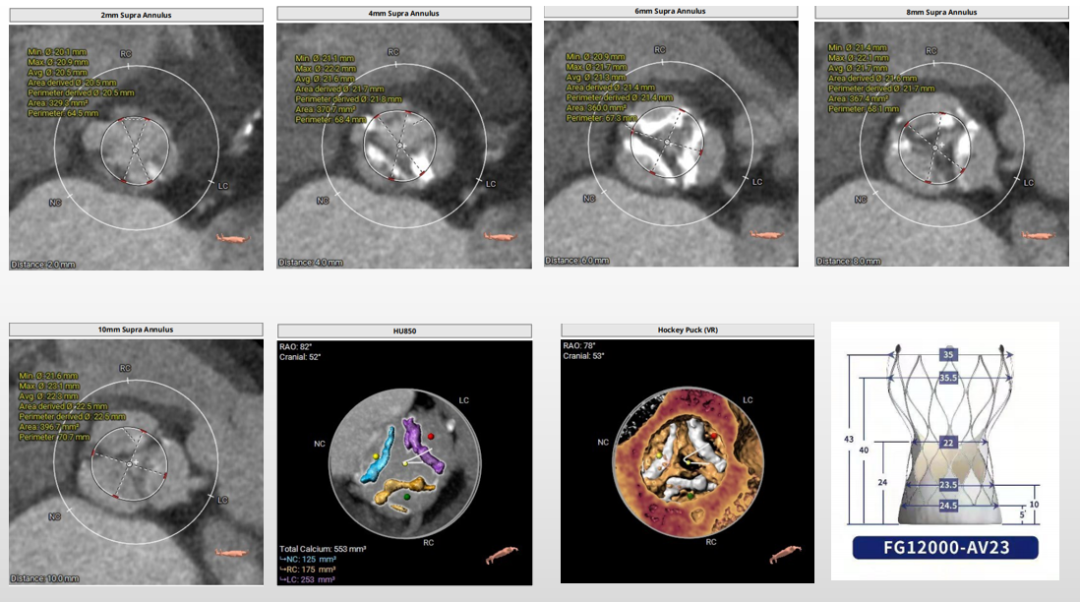

瓣环上解剖结构评估

中度钙化,瓣上6-8mm限制最重,根据瓣环及瓣上情况,选18mm球囊预扩、AV23瓣膜。

重度钙化,瓣上4-8mm限制最重,根据瓣环及瓣上情况,选20mm球囊预扩、AV23瓣膜。

无钙化,根据瓣环及瓣上情况,选AV29瓣膜。